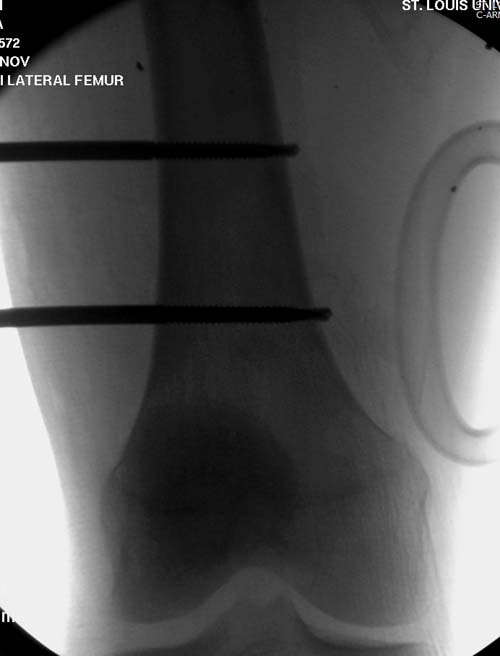

В замкнутом без перелома пространстве во время риминга повышается

давление внутри канала, и имеется риск тромбообразования. Для

профилактики и для дренажа - канюлированный винт 6.5 мм в дистальной

части бедра. Обработку заканчивают культурой из раны и канала. Иногда

Рекомендуется: антибиотический гвоздь на цементе. Нагрузку можно

разрешить сразу, перелом сросся давно!